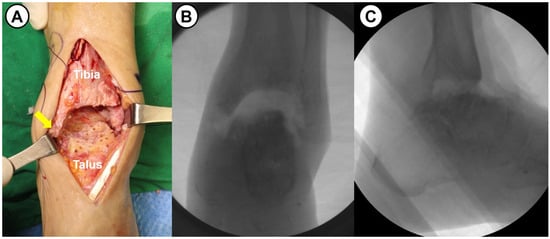

Figure 3.

(A) Intraoperative photograph shows subchondral preparation (multiple drilling) following the removal of remaining cartilage and necrotic bone in a 63-year-old female patient with avascular necrosis of the talus (arrow: medial malleolus). (B,C) Intraoperative fluoroscopic images show a large defect space between tibial plafond and talar dome.

All surgeries were performed by a single senior surgeon with over 15 years of experience. Shortening ankle arthrodesis basically consisted of fibular osteotomy, internal fixation with anterior fusion plate, and autogenous bone grafting. A 10 cm sized anterior midline longitudinal skin incision was made and careful soft tissue dissection between the tibialis anterior and extensor hallucis longus tendons was performed to approach into the ankle joint. Following excision of the joint capsule, the remaining cartilage and osteophytes were removed, and sufficient subchondral preparation with multiple drilling to stimulate bone-marrow bleeding was performed (Figure 3). In cases of failed TAA, all prosthesis and metallosis debri were meticulously removed. To maximize the contact area and to minimize the large defect space between tibial plafond and talar dome, fibular osteotomy with protection of the anterolateral neurovascular bundle was performed approximately 1–5 cm above the upper margin of the distal tibiofibular syndesmosis (see Figure 4). Following a transverse osteotomy, the proximal and distal parts were completely displaced, and a segmental bone fragment of about 1–3 cm was harvested from the proximal part if necessary for bone grafting. Then, the distal tibiofibular syndesmosis was dissociated by dissecting the interosseous ligament and anterior and posterior tibiofibular ligaments. The talus was proximally repositioned with maximal compression force. Any remaining defect was filled with an autograft cancellous bone (an average of 11.8 cc) harvested from the proximal tibial metaphysis. With the ankle placed in neutral position, two partially threaded cannulated screws (6.5 mm in diameter) were inserted in a cross-articular manner. Finally, the Titanium Ankle Fusion Plating System (Arthrex, Naples, FL, USA) was secured with locking compression screws (Figure 5). Under C-arm guidance, the final alignment of the ankle and implant position were checked.